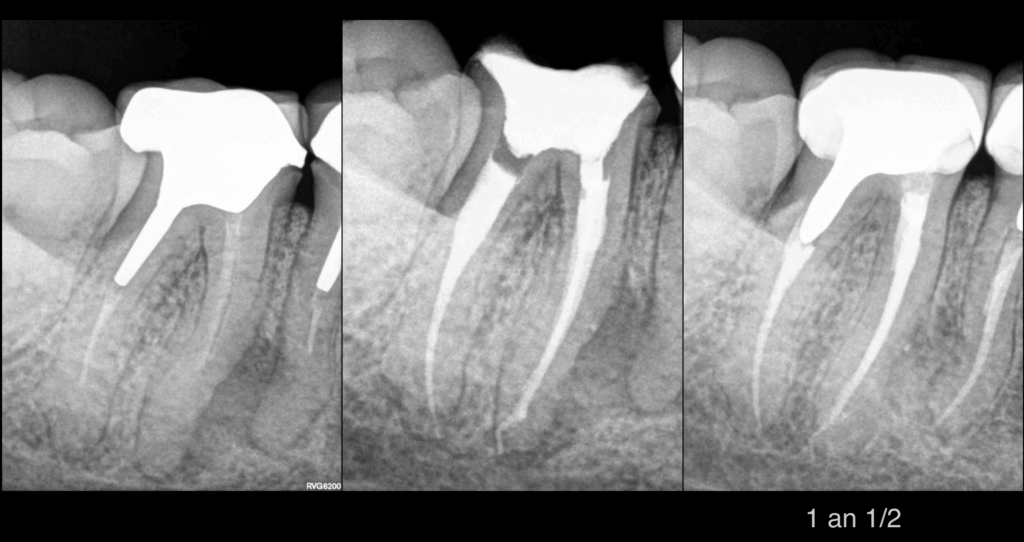

🦷 Dents n°46 et 47

📍 𝐋𝐞́𝐬𝐢𝐨𝐧 𝐚𝐩𝐢𝐜𝐚𝐥𝐞 𝐞𝐭 𝐥𝐚𝐭𝐞́𝐫𝐨-𝐫𝐚𝐝𝐢𝐜𝐮𝐥𝐚𝐢𝐫𝐞 entre 46 et 47

❓ Quelle en est la cause ? 46 ? 47 ? Les deux ?

📌 ATCD de douleur au niveau de cette zone, mais situation asymptomatique le jour de la consultation

🔍 𝐋𝐞́𝐬𝐢𝐨𝐧 𝐝𝐞 𝐥𝐚 𝐟𝐮𝐫𝐜𝐚𝐭𝐢𝐨𝐧 au niveau 46, sans sondage parodontal → origine endo

🔁 𝐑𝐞𝐭𝐫𝐚𝐢𝐭𝐞𝐦𝐞𝐧𝐭 𝟒𝟔 𝟒𝟕 :

En mésial de 46, impossible d’obtenir la perméabilité en raison d’une oblitération canalaire des canaux MV et ML.

📸 À 1 an ½ :

✅ 𝐆𝐮𝐞𝐫𝐢𝐬𝐨𝐧 𝐝𝐞 𝐥𝐚 𝐥𝐞́𝐬𝐢𝐨𝐧 𝐚𝐩𝐢𝐜𝐚𝐥𝐞 𝐞𝐭 𝐥𝐚𝐭𝐞́𝐫𝐨-𝐫𝐚𝐝𝐢𝐜𝐮𝐥𝐚𝐢𝐫𝐞

✅ 𝐆𝐮𝐞𝐫𝐢𝐬𝐨𝐧 𝐝𝐞 𝐥𝐚 𝐥𝐞́𝐬𝐢𝐨𝐧 𝐝𝐞 𝐥𝐚 𝐟𝐮𝐫𝐜𝐚𝐭𝐢𝐨𝐧 𝟒𝟔